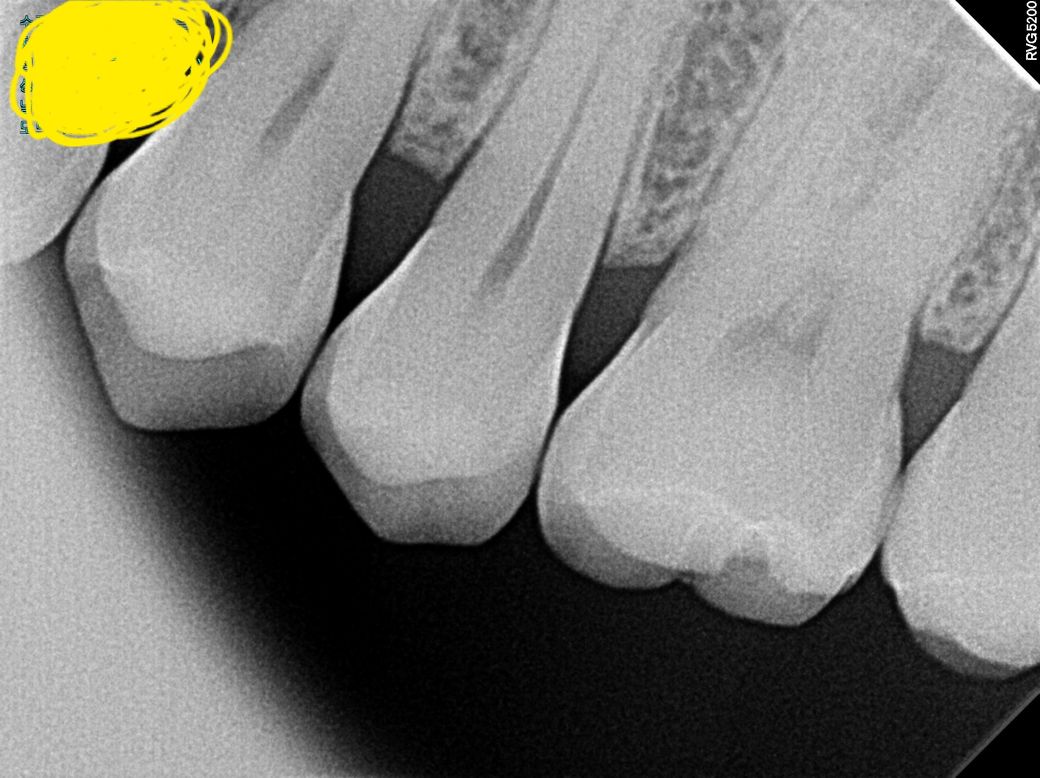

치근단사진좀 살펴봐 주세요. (치식과 충치여부)

치아 치근단사진 에서 보이는 치아가 몇번 (치식)

인지요? 충치나 파절이 있는지 궁금합니다.

겉으로는 검은색이 보이는데 오른쪽 위 뒤에서 세번째.

치근단사진상 보이는 것이 있는지요?

엑스레이 상으로는 치아 사이는 크게 충치가 잇어 보이진 않습니다. 사진에서 보이는 큰 어금니의 씹는면은 약간 깨진부위가 잇는거 같습니다.

25번 치아이고 방사선사진상 충치나 파절은 보이지 않습니다

육안으로 보이는 검은색 선은 초기충치일 가능성이 있습니다